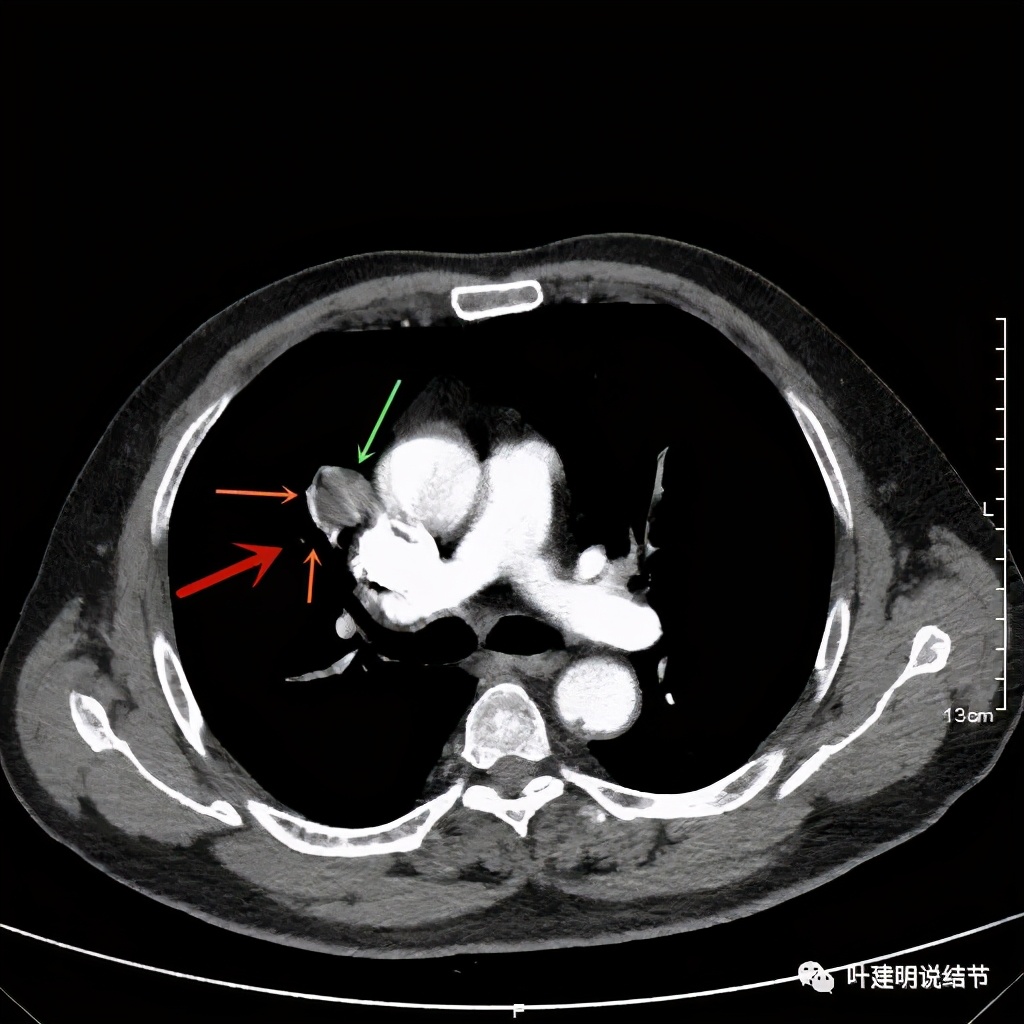

上图示病灶边缘过于光滑(绿色);局部有点状钙化(蓝色)

上图示病灶边缘过于光滑(绿色);血管贴边(桔色);

上图示病灶边缘过于光滑(绿色);血管贴边走行(桔色)

以上几图也示病灶边缘过光(绿色);血管贴边,感觉没受侵犯(桔色)